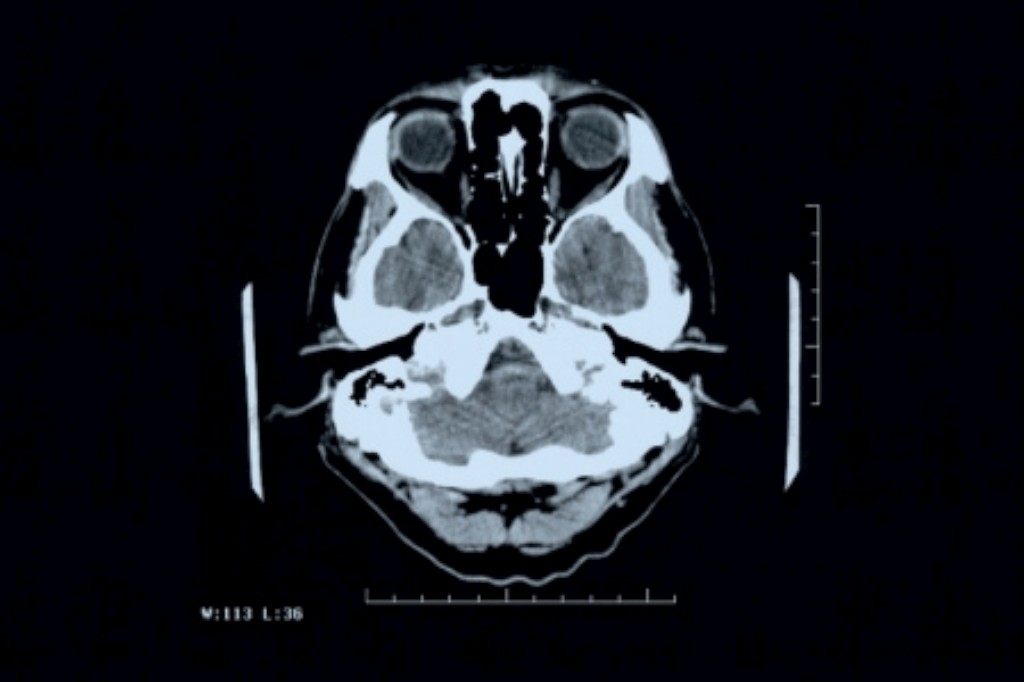

A equipa testou o Bexarotene e verificou que se liga a um receptor das células que provoca a produção da Apo-E. Nos ratinhos que tomaram a droga, em apenas seis horas, foi degradado um quarto da Beta amilóide que estava solúvel no cérebro. Mais, nos doentes de Alzheimer esta proteína acumula-se no cérebro em forma de placas, uma das características mais fortes desta patologia. Mas nos roedores tratados, mais de metade das placas foram degradadas em apenas 72 horas e ao final de algum tempo 75% das placas desapareceram. Estes efeitos nunca foram conseguidos em nenhuma outra droga utilizada para tratar doentes com Alzheimer.